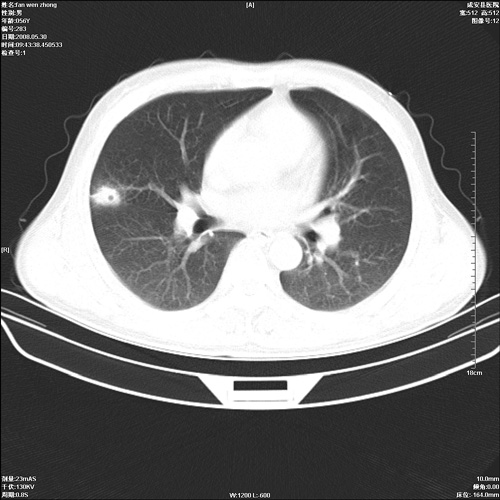

病人 男 56岁 一周前高热,体温达39-40度,经抗炎治疗后,体温渐降,达37,5-38度,轻微咳嗽,胸部不适 查白细胞为1.3万 行ct检查,请分析。

双肺内可见多发结节状病灶,并见小空洞,病人高热,白血球增高,应该是典型的迁徙性肺脓肿(多为金黄色葡萄球菌感染)。查一下口腔等其它部位有无感染灶。

双肺内可见多发结节状病灶,并见小空洞,病人高热,白血球增高,应该是典型的迁徙性肺脓肿(多为金黄色葡萄球菌感染)。建议治疗后复查.